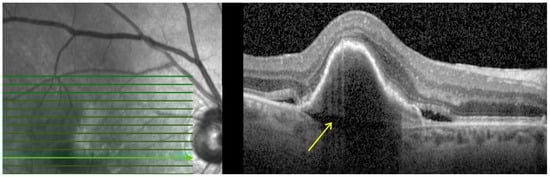

- Prechoroidal cleft (PCC): Defined as hyporeflective space between the RPE fibrovascular tissue and Bruch membrane as shown in Figure 4. PCCs are closely associated with a poor visual prognosis and increased risk of submacular hemorrhage or RPE tear [15]. The origin of the cleft has been attributed to a possible accumulation of the fluid generated by the fibrovascular tissue. However, its correlation with lesion activity and treatment remains unknown [32].